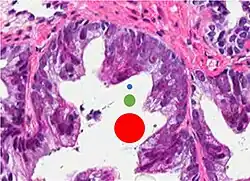

Glomerulation.

- Relatively common and highly specific

- [4]

- Multiple nucleoli

- Eccentric nucleoli[4]

Acinar adenocarcinoma with multiple nucleoli.

Acinar adenocarcinoma with double and eccentric nucleoli.